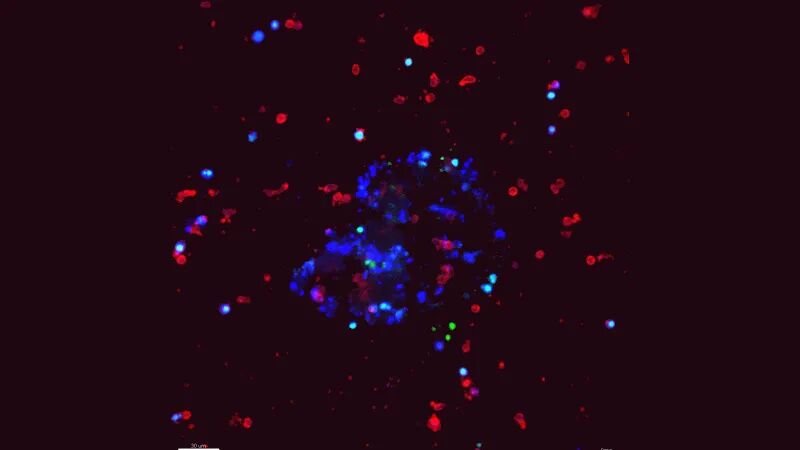

▼NK细胞在对抗癌细胞

图片

▲图源“Isaac Chan, M.D,Ph.D”,版权归原作者所有,如无意中侵犯了知识产权,请联系我们删除

注:蓝色肿瘤类器官,在被红色NK细胞包围。